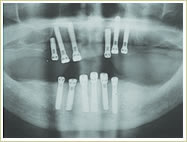

79歳 男性 インプラント埋入数:12本 画像拡大

治療前

治療中

治療中治療後